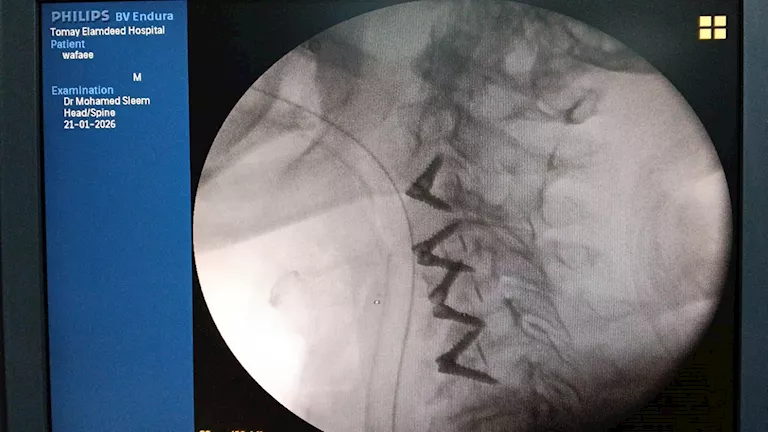

وبإجراء الفحوصات الطبية والأشعات اللازمة، تبين إصابة المريض بانزلاق غضروفي عنقي متعدد على أربعة مستويات، ما أدى إلى حدوث كدمة بالحبل الشوكي وضيق كامل بالقناة الشوكية العنقية، وهي من الحالات شديدة الخطورة التي تستدعي تدخلاً جراحيًا دقيقًا وعاجلًا.

وجرى تجهيز الحالة طبيًا من خلال إجراء جميع الفحوصات والتحاليل اللازمة، قبل أن يخضع المريض لجراحة ميكروسكوبية دقيقة ومعقدة، تم خلالها استئصال الغضاريف المنزلقـة، وتركيب أقفاص عنقية مثبتة بدعامات ذاتية (Stand-alone) على أربعة مستويات، وذلك باحترافية عالية، مع خروج المريض من غرفة العمليات في حالة مستقرة وآمنة.